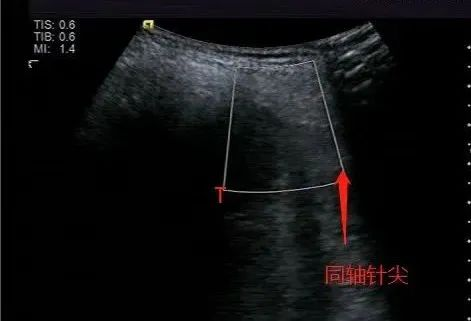

术中B超实时引导和确认同轴针处于理想位置